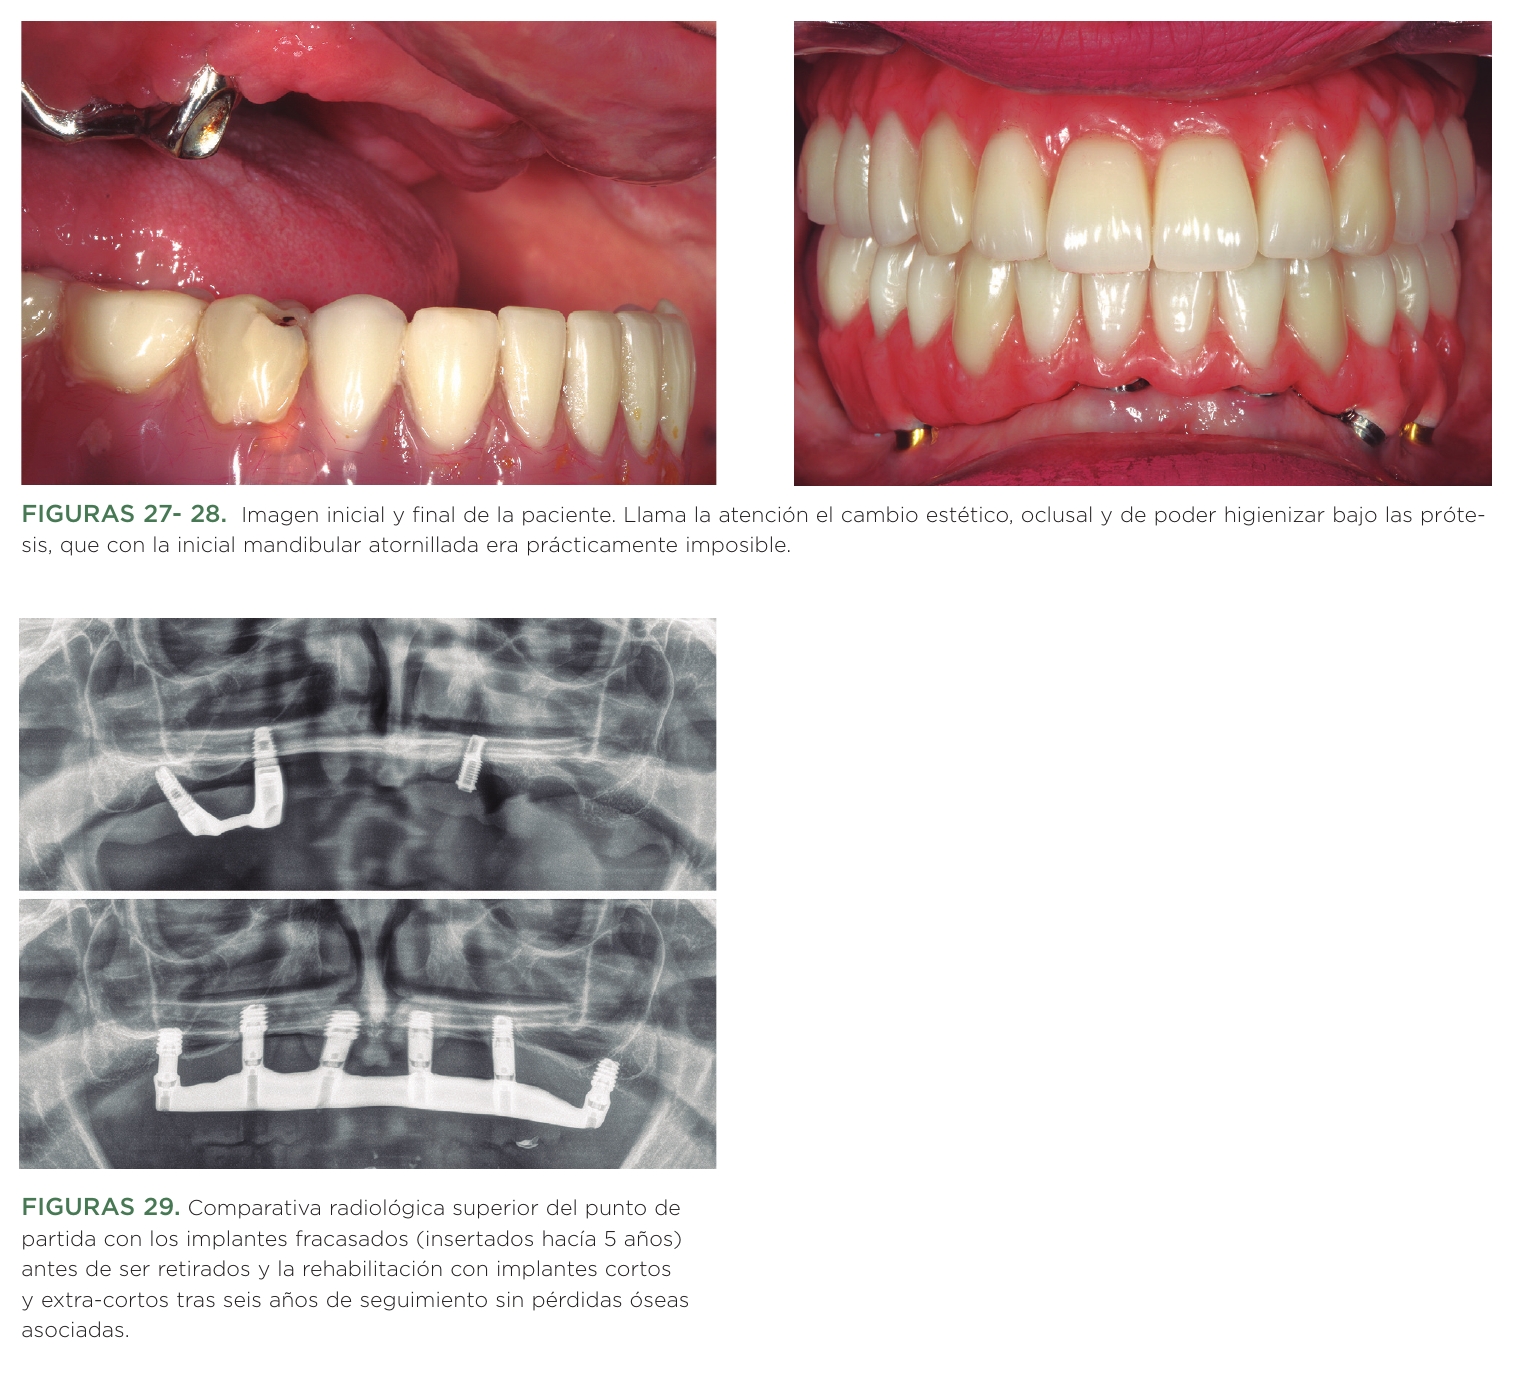

Tras las pruebas, se transforman ambos encerados en las prótesis definitivas, que serán híbridas de resina, debido al amplio espacio interoclusal a rehabilitar. Se llevan a cabo mediante estructuras metálicas fresadas por cad-cam y sobre ellas se construye posteriormente toda la resina. Tanto la rehabilitación superior como la inferior son atornilladas a través de transepiteliales (figuras 21-26). En la radiografía panorámica final vemos además como ahora los implantes inferiores tienen una distribución biomecánica más adecuada evitándose en gran medida los momentos flexores de los voladizos distales durante la masticación, aunque uno de los implantes iniciales se ha conservado al no presentar patología periimplantaria y por deseo expreso de la paciente (figura 27).

Se ha mejorado por lo tanto la higiene y la carga que reciben los implantes en el arco inferior además de la estética y la función en ambos maxilares (figuras 27- 28), como vemos en las imágenes comparativas de antes y después. La paciente continúa en seguimiento y seis años después la rehabilitación se mantiene sin incidencias ni pérdidas óseas asociadas, muy notable como resaltamos en la comparativa de la rehabilitación del maxilar superior con extrema atrofia vertical (figura 29).